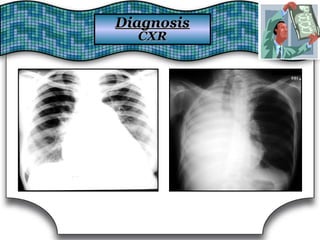

Chest X Ray (CXR)Chest X Ray (CXR)

Chest RadiographChest Radiograph Suggestive DiagnosisSuggestive Diagnosis

Cardiomegaly, increasedCardiomegaly, increased

pulmonary vascular distributionpulmonary vascular distribution

Chronic heart failure, mitral valve stenosisChronic heart failure, mitral valve stenosis

Cavitary lesionsCavitary lesions Lung abscess, TB, necrotizing carcinomaLung abscess, TB, necrotizing carcinoma

Diffuse alveolar infiltratesDiffuse alveolar infiltrates Chronic heart failure, pulmonary edema, aspirationChronic heart failure, pulmonary edema, aspiration

Hilar adenopathy or massHilar adenopathy or mass Carcinoma, metastatic disease, infectionCarcinoma, metastatic disease, infection

HyperinflationHyperinflation COPDCOPD

Lobar or segmental infiltratesLobar or segmental infiltrates Pneumonia, thromboembolism, obstructing carcinomaPneumonia, thromboembolism, obstructing carcinoma

Mass lesion, nodules, granulomasMass lesion, nodules, granulomas

Carcinoma, metastatic disease, Wegener'sCarcinoma, metastatic disease, Wegener's

granulomatosis, septic embolism, vasculitidesgranulomatosis, septic embolism, vasculitides

Patchy alveolar infiltratesPatchy alveolar infiltrates

Bleeding disorders, idiopathic pulmonaryBleeding disorders, idiopathic pulmonary

hemosiderosis, Goodpasture's syndromehemosiderosis, Goodpasture's syndrome